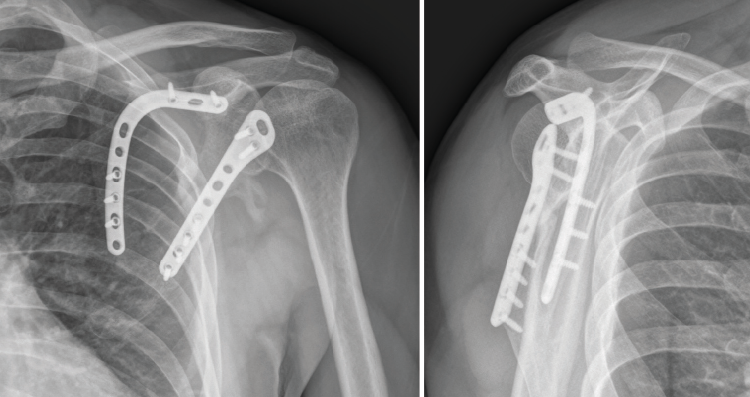

Los márgenes mediales de la escápula tienen un espesor aproximado de 10-14 mm y, por ello, permiten una sujeción cortical densa para el posterior montaje de la placa. Una vez obtenida una visualización óptima del foco de fractura, obtenemos las placas que vamos a utilizar, que ya habíamos seleccionado previamente gracias a nuestro modelo tridimensional que utilizamos en la planificación preoperatoria. En este caso, optamos por colocar 2 placas anatómicas premoldeadas Scapula Plating System®, de la casa comercial Acumed, una en ‘L’ invertida, para el borde medial, y otra recta, con ensanchamiento lateral para los tornillos glenoideos, para el borde lateral (Figura 10).

Una vez colocados los tornillos, comprobamos la correcta reducción de la fractura mediante control fluoroscópico. Dejamos un drenaje aspirativo subcutáneo, que retiraríamos a las 24 horas de la cirugía, momento en el que hacemos el primer control radiográfico. El paciente sale del quirófano con un cabestrillo que mantenemos durante 4 semanas, en las cuales le permitimos iniciar ejercicios de péndulo. Entre la segunda y la cuarta semana tras la cirugía el paciente comienza a realizar ejercicios pasivos en todo el rango de movimiento. A partir de la cuarta semana, son permitidos los ejercicios activo-asistidos hasta la sexta semana, momento en el que se le permite realizar ejercicios activos, una vez que se espera encontrar signos de consolidación clínicos y radiológicos.

En el control de la cuarta semana postoperatoria se observaron signos de consolidación radiográfica y ausencia de dolor sin medicación analgésica (escala visual analógica = 0). Al final del seguimiento (7 meses tras el tratamiento quirúrgico) el paciente conseguía una movilidad activa consistente en 120° de flexión y de abducción, una rotación interna suficiente para tocar con el pulgar su espalda a nivel de la vértebra T12 y una rotación externa en la que conseguía llevarse la mano a la nuca sin antepulsar el codo. Se evidenció, no obstante, una leve pérdida de fuerza con respecto al hombro contralateral. Tras 112 días de baja laboral desde el día del accidente, el paciente fue reincorporado a su puesto de trabajo laboral sin secuelas reseñables y con el control radiográfico que se muestra en la Figura 11.